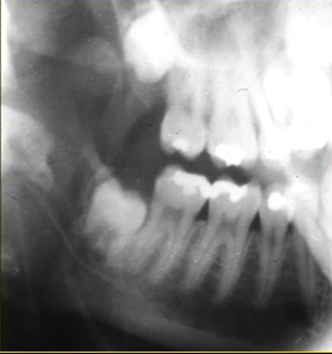

oblique lateral technique allows you to take extraoral radiographs

image receptor is placed outside the mouth and against the side of the face

resultant radiographs are larger and show anatomical structures in both jaws

direction of Xray beam on this skull

for right hand side - tube head left and receptor opposite - passes between the cervical spine and the left ascending ramus of the mandible - viewed like you are looking at the patient’s right cheek

posterior edge of left side

radiolucent band around the posterior part of the body of the mandible

created by inferior dental nerve and blood vessel, created by the inferior dental canal

the edges of the canal can be seen as thin, white radiopaque lines → ‘tram lines’